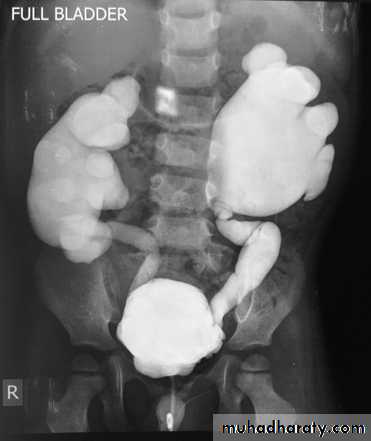

KUB

Multiple bilateral renal stonesStaghorn stone needs PCNL